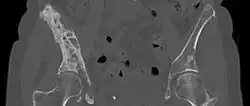

3D rendered CT scan of bone metastases of the hip bone, in a 60 year old woman with parotid gland cancer. Large lesions are seen on the ilium on the more distant side. Involvement of the vertebral column has caused a compression fracture. | |